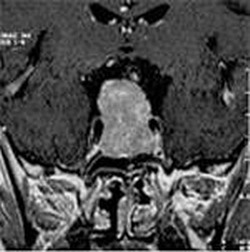

ОПУХОЛИ ГОЛОВНОГО МОЗГА

Методом выбора в лечении большинства опухолей головного мозга и метастатических опухолей головного мозга являются микрохирургические операции, которые проводятся с помощью интраоперационной нейронавигации.

- При локализации опухоли, расположенной вблизи особенно важных центров мозга, вначале проводится интраоперативная мозговая картография (intraoperative brain mapping).

- При микрохирургическом лечении собственных опухолей мозга (глиом) дополнительно мы используем интраоперационную флюоресцентную навигацию с применением ALA (5-аминолевулиновой кислоты).